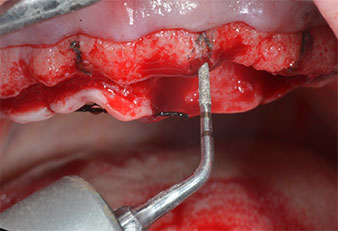

Ein flammenförmiges, diamantiertes piezochirurgisches Instrument (Piezomed I1) wurde verwendet, um die Implantatpositionen zu markieren und die Pilotpräparationen durchzuführen (Abb. 3). Dabei wurde darauf geachtet, eine Auf- und Abbewegung mit reduzierter Leistung, voller Spülung und niedrigem Druck (unter 300 g) anzuwenden. Als Nächstes wurde ein Pilotinstrument (Piezomed I2A/I2P) zur initialen Erweiterung der Implantatlager auf einen Durchmesser von 2 mm verwendet (Abb. 4), gefolgt von einem 3-mm-Instrument (Abb. 5).

Im vorliegenden Fall wurden die Instrumente Z25P und Z35P wegen des relativ weichen posterioren Knochens nicht verwendet, der problemlos mit dem I3A/I3P bearbeitet werden konnte.

Wegen des relativ harten Knochens (D2) an den Positionen 11 und 21 wurden die 10 mm langen Implantatlager in diesem Bereich abschließend mit einem 4-mm-Spiralbohrer, dem chirurgischen Winkelstück WS-75 L von W&H und dem W&H Implantmed Implantologiemotor in Verbindung mit dem optionalen W&H Osstell ISQ module präpariert. Im Gegensatz dazu wurde der weiche Knochen der Implantatlager im Seitenzahnbereich mit dem Piezomed I3P auf den abschließenden Durchmesser von 3 mm erweitert. Die Implantate wurden dann transgingival eingesetzt, die Einheildauer betrug drei Monate (Abb. 6-10). Die vorhandene Prothese wurde auf vier provisorischen Implantaten abgestützt (Abb. 8).